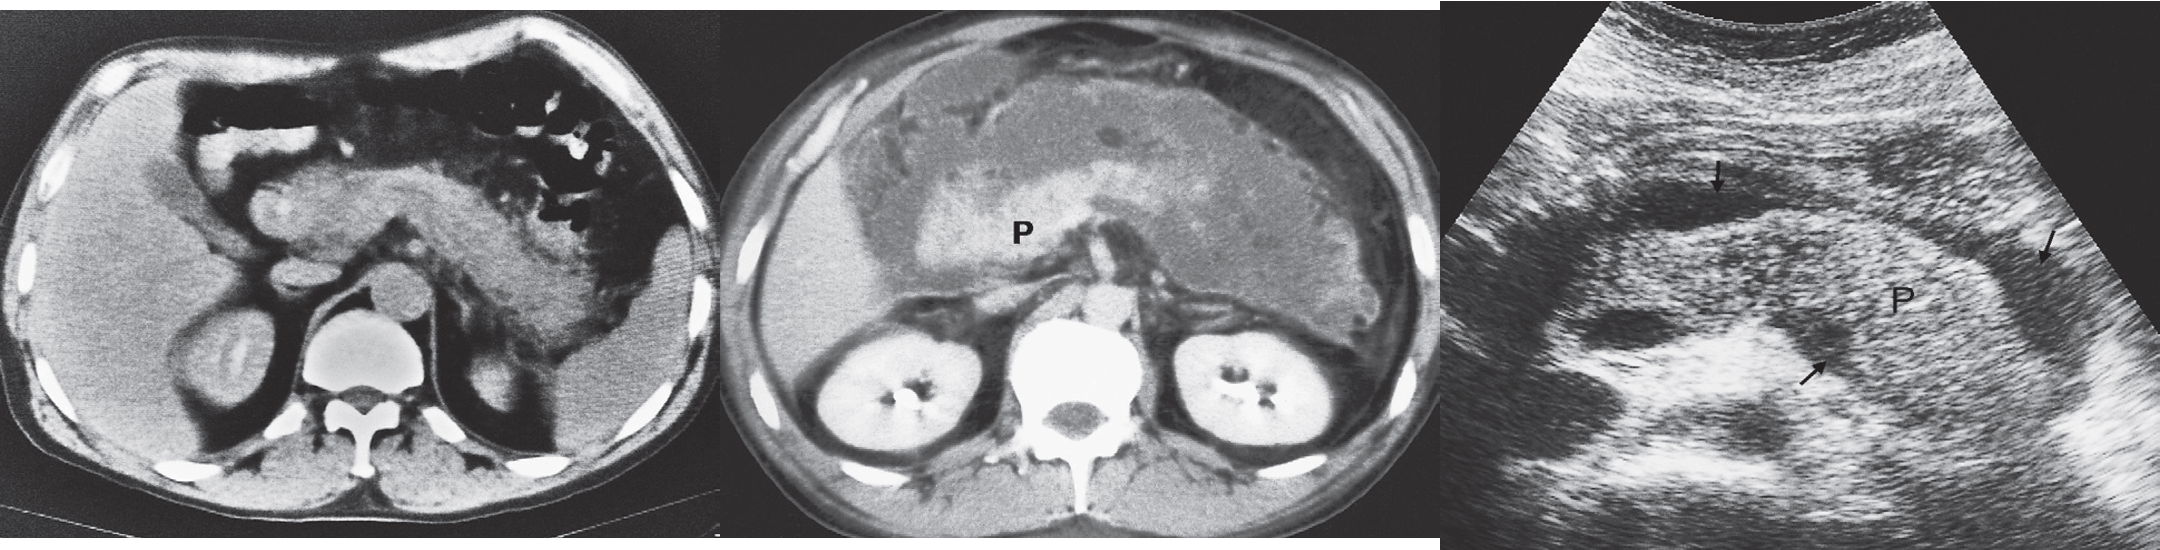

CT and ultrasound findings:

The pancreas is usually enlarged, often diffusely, and may show irregularity of its outline.

There may be low density areas at CT and echo-poor areas at sonography, representing oedema.

Peripancreatic fluid and/or ascites.

- (a) CT scan showing diffuse enlargement of pancreas w/ ill-defined edges.

- (b) CT scan showing considerable inflammation around the pancreas (P).

- (c) Transverse ultrasound scan showing a swollen pancreas (P) with some fluid around the pancreas. defined margins, irregular, bulky